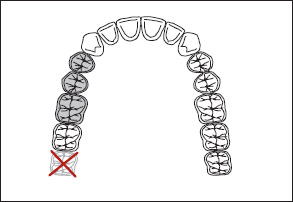

1. Classification should follow rather than precede extractions that might alter the original classification (Fig 1-22).

Fig 1-22 If extractions are to be performed, classification should follow rather than precede the extractions. In this instance, the indicated extractions yield a Kennedy Class II, Modifcation 1 arch.